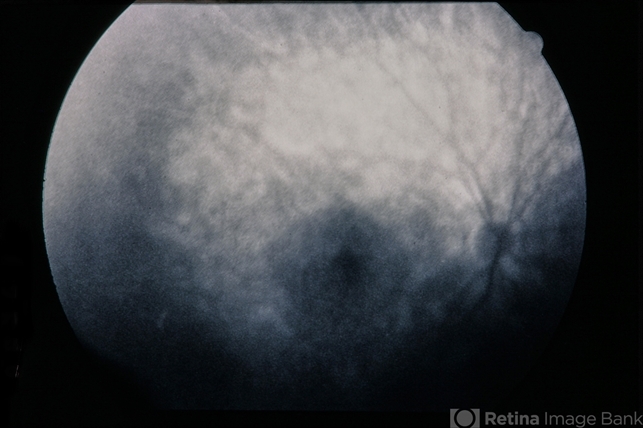

Plaquenil Toxicity

David Callanan, MD

60-year-old female with plaquenil toxicity.